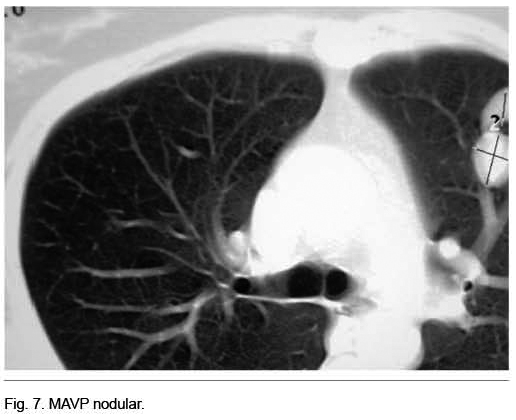

Mujer de 53 años con antecedentes personales de epistaxis recurrentes. Derivada por el oncólogo por el hallazgo de múltiples nódulos pulmonares a nivel de la RxTx y TC.

Se destacaba la existencia de múltiples telangiectasias mucocutáneas (Figura 6). Se realizó angioTC que confirmó el diagnóstico de MAVP múltiples (Figura 7); dos a nivel de lóbulo superior izquierdo y otra a nivel de lóbulo inferior derecho. Se realizó arteriografía y, simultáneamente, la embolización de las dos MAVP izquierdas, quedando una malformación a nivel del lóbulo inferior derecho simple de 3 mm (Figura 8).

El tercer caso se trata de una paciente de 53 años con antecedentes de epistaxis recurrentes, anemia ferropénica, en estudio de etiología no aclarada y múltiples telangiectasias mucocutáneas. Fue derivada por el oncólogo por presentar nódulos pulmonares bilaterales, catalogados de probable secundarismo pulmonar sin diagnóstico anátomopatológico. En esta paciente la sospecha diagnóstica inicial fue de ROW asociado a MAVP. Los estudios de imágenes fueron fundamentales para poder arribar al diagnóstico correcto.

En cuanto a los métodos de diagnóstico utilizados en los tres casos, debemos de jerarquizar que la RxTx fue patológica en todos; ésta es anormal en el 98% de los casos(2). La gasometría arterial ventilando espontáneamente al aire confirmó la presencia de insuficiencia respiratoria crónica tipo I en los tres casos, y sin corrección luego de la administración de oxígeno por 30 minutos, permitiendo afirmar el mecanismo de shunt. En el caso número 1 también se destacaba clínicamente la presencia de platipnea y ortodeoxia. La angio TC fue el método de diagnóstico en los tres casos, con un excelente rendimiento. Se trata de una técnica sensible, de bajo costo, que permite establecer el diagnóstico de MAVP. Permite la valoración del tamaño, topografía y angioarquitectura, así como el seguimiento de la lesión luego de realizado tratamiento(5). En los tres casos la confirmación diagnóstica fue mediante la angioTC, permitiendo realizar la arteriografía sólo con una finalidad terapéutica. Los tres pacientes fueron sometidos a embolización con coils fibrilares de platino, con excelente evolución clínica. Su objetivo es la oclusión de la arteria aferente (única o múltiple) con el fin de excluir la comunicación arteriovenosa patológica, preservando el máximo posible de parénquima funcionante. Las indicaciones de tratamiento se fundamentan en la elevada morbimortalidad histórica de estos pacientes. Fundamentalmente debido a complicaciones neurológicas, las cuales se observan hasta en 30% de los pacientes no tratados. A esto debemos sumarle las importantes secuelas neurológicas, muchas de ellas invalidantes, a las cuales quedan expuestos. A su vez, los mismos autores reportaron un riesgo de padecer un “stroke” de 1,5% por año si la MAVP presenta una arteria aferente con un diámetro igual o mayor de 3 mm(2-9). Los materiales más utilizados en la actualidad para la embolización son los coils(1-8) y los tapones vasculares(10,11). Los coils son espirales metálicas, expansibles, de diferentes diámetros y longitudes, según el vaso o estructura a tratar y que, por lo general, se encuentran recubiertos de fibras artificiales que aumentan su potencial trombogénico(12).